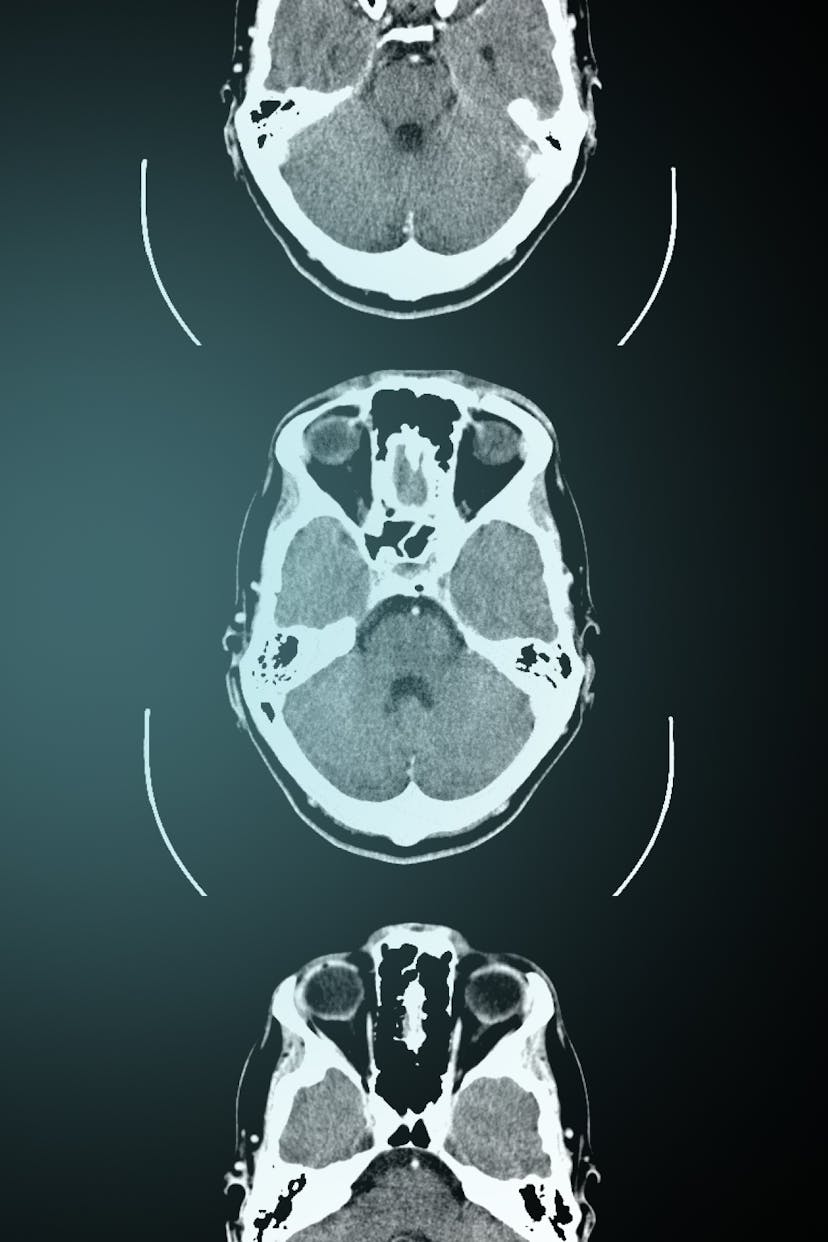

Representations of the corpse have transfixed society since antiquity. Whether visualised in portraiture or vanitas, embodied in effigies or death masks, or recorded on photographs or x-rays, the dead can only appear to the living through their images.

It has been suggested by philosophers, anthropologists, sociologists, and legal scholars that images enable the corpse to appear and speak to the living. The practice of visualising the corpse has shaped an inventory of techniques for representing death in the domains of art, medicine and law. In a world where death touches us in many ways, from playing cards to horror films, public executions to coronial investigations, images of the corpse remind us that the dead never disappear. Whether they are memorialised in art, pathologised in medicine, misrepresented in law or simply linger in the empty spaces of galleries, hospitals or courtrooms, the corpse always remains at work.